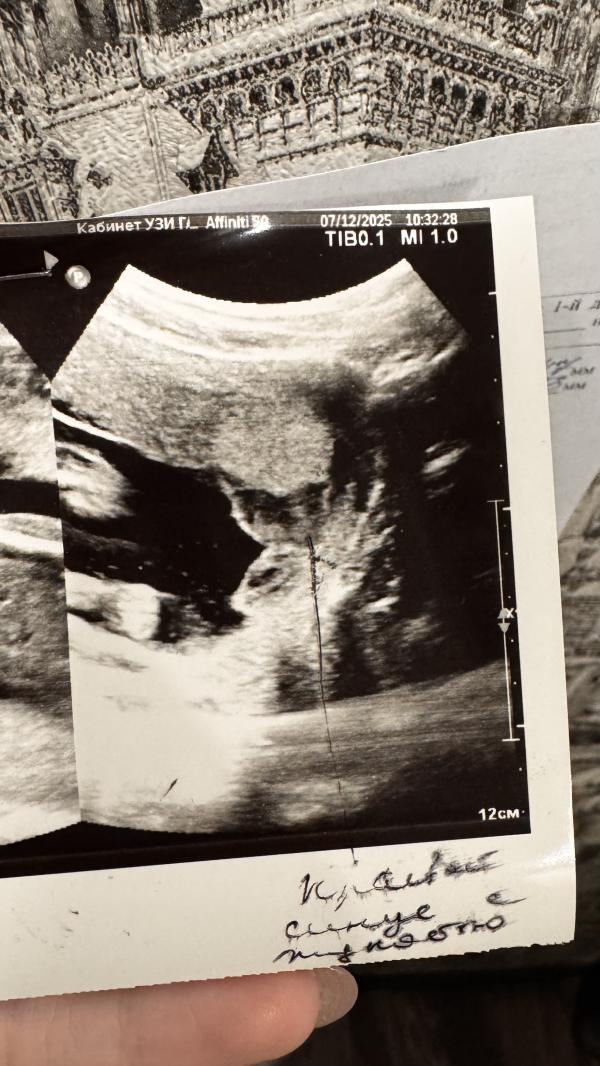

По гематоме (2 фото) сказали, что это вовсе не гематома, а скопление жидкости - крови. Сказали это не страшно, это не отслойка и к ней она не имеет никакое отношение. Она либо лопнет и одномоментно у меня будет много крови, но в один момент, если это без боли произойдет, значит все хорошо и просто вышла это фигня. Либо она может рассосаться и не выходить. Посмотрим, что скажет гинеколог на это.